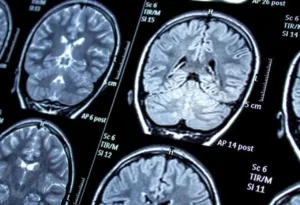

Healing Young Minds: The Journey to Recovery from Traumatic Brain Injuries

Traumatic Brain Injuries (TBI) in children and adolescents represent a significant public health concern, affecting millions of young lives every year. Whether due to car accidents, falls, sports injuries, or…